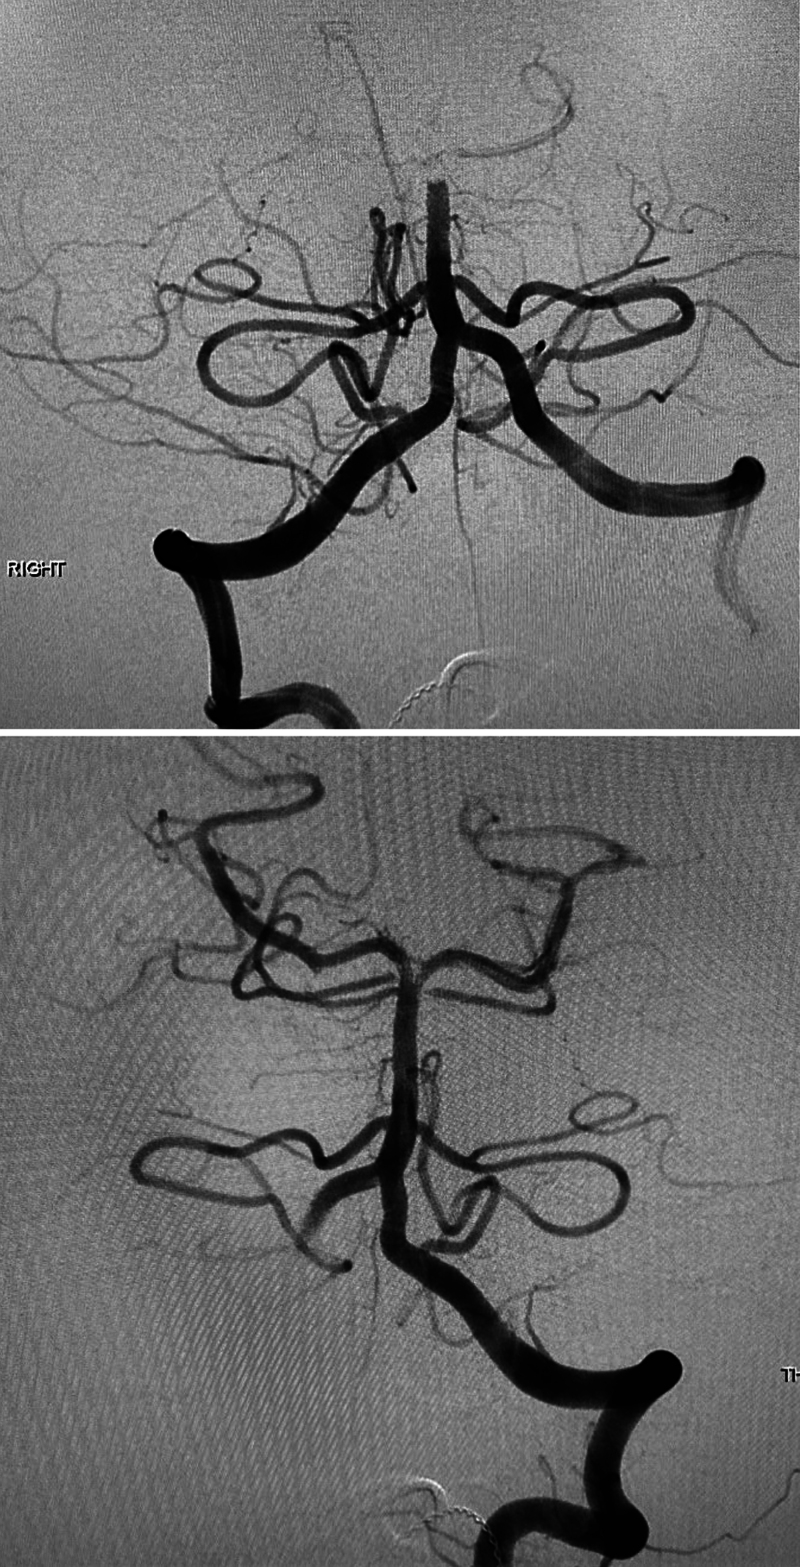

Observations: This case report discusses the management of a 13-year-old male with recurrent basilar artery occlusions and an associated vertebral artery dissection. Initially presenting with acute ischemic stroke symptoms, the patient underwent a successful thrombectomy with significant improvement in neurological function. He experienced a second stroke due to another basilar artery occlusion, which was subsequently treated by a thrombectomy. Further investigation revealed a vertebral artery dissection with a pseudoaneurysm, likely contributing to the stroke recurrence. Treatment adjustments included transitioning from aspirin to clopidogrel when aspirin resistance concern was noted, and finally apixaban therapy when the dissection was discovered. The patient remained stable without stroke recurrence.